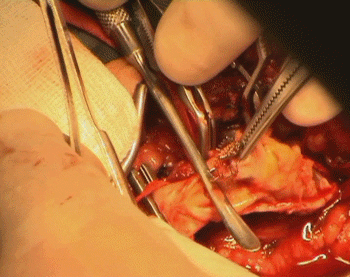

The patient under G.A with nasal intubation, in case he needs high dissection, were performed. Incision was made to expose the distal 3 cm of the CCA and the ICA until the upper edge of the stint was felt. The ECA was dissected and the superior thyroid artery. All was done with the BP of the patient kept at 170/100 mm Hg. and continuous cover of the patient with 500 units of heparin/hour. An-Argyle-like tube was prepared in case, but when it was found that, the back flow of the ICA was weak, it was decided that, no need for such shunting.  For technical details of the operative details, you can refer to this article.

The atheroma was completely occluding the soft construct of the stint, with minimal clot inside the very shallow space inside the compressed stint. After removal of the stint, it regained its cylindrical configuration, as seen in the lower pictures.

Water-tight closure of the vascular wall with 6 zero nylon and the carotid bulb and major branches were checked for the flow and presence of bleeding points. Meticulous heamostasis and ready-vac drain  No 8 left in the wound.

Exposure of the atheroma in the CCA. Sharp cut of the atheroma at the CCA.

The lower edge of the stent is seen inside the atheroma. The stent and atheroma completely occluding the ICA.

Fine dissection is going on. The atheroma is removed from the superior thyroid artery.

The atheroma is dissected from th ECA. Cutting the atheroma from the ECA.

Further cleaning of the debris after removal of the mess. The carotid bifurcation after repair with nylon 6 zero.

Stages of atheroma with stint removal. Notice that the atheroma was extending far to the ECA and even the STA!